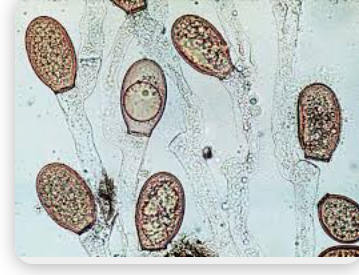

Yeast cells

round or ovoid cells that produce daughters by budding

Candida Species Morphology

Form yeast-like cells (blastoconidia), pseudohyphae and true hyphae in tissue